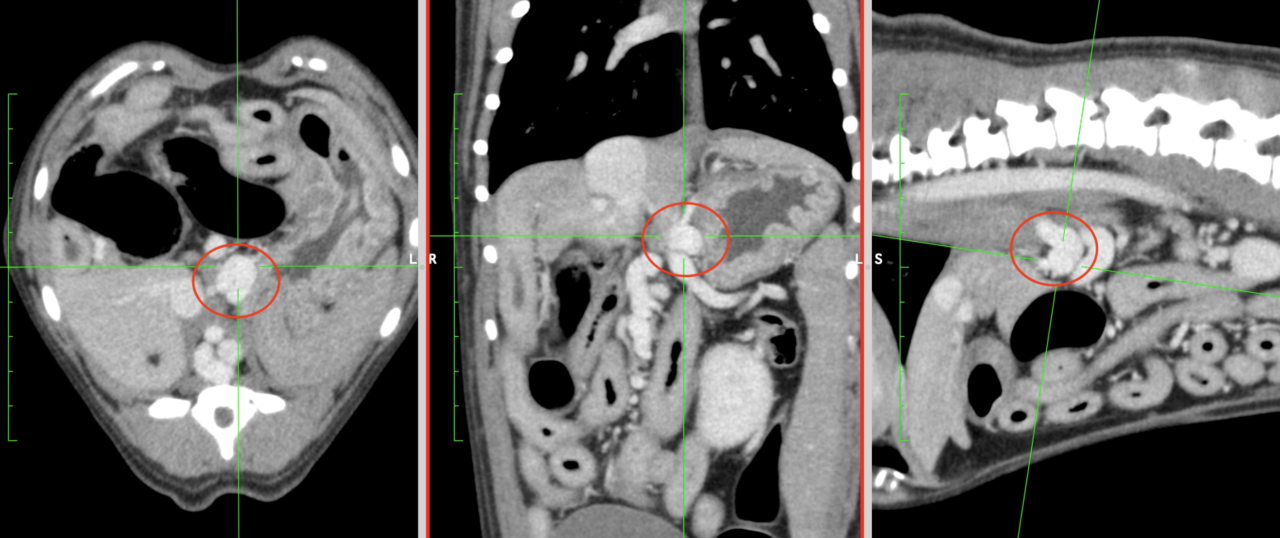

門脈体循環シャントのCT画像(赤丸がシャント血管)

血液検査(アンモニアやTBAが高い)やレントゲン検査(肝臓が小さい)、尿検査(尿酸アンモニウム結晶がみられる)、超音波検査(肝臓が小さい、異常血管がみえる)で疑わしい場合、最終的にはCT検査で診断します。